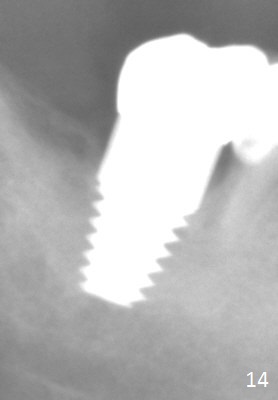

The patient returns for final restoration 5.5 months postop; it appears that the distal gap has disappeared (Fig.13 *). There is no bone loss 26 months post cementation (Fig.14). The lamina dura-like dense bone forms coronally 3 years 4 months post cementation (Fig.15 *). The 8 mm implant remains buried in the bone 5 years 4 months post cementation (Fig.16).